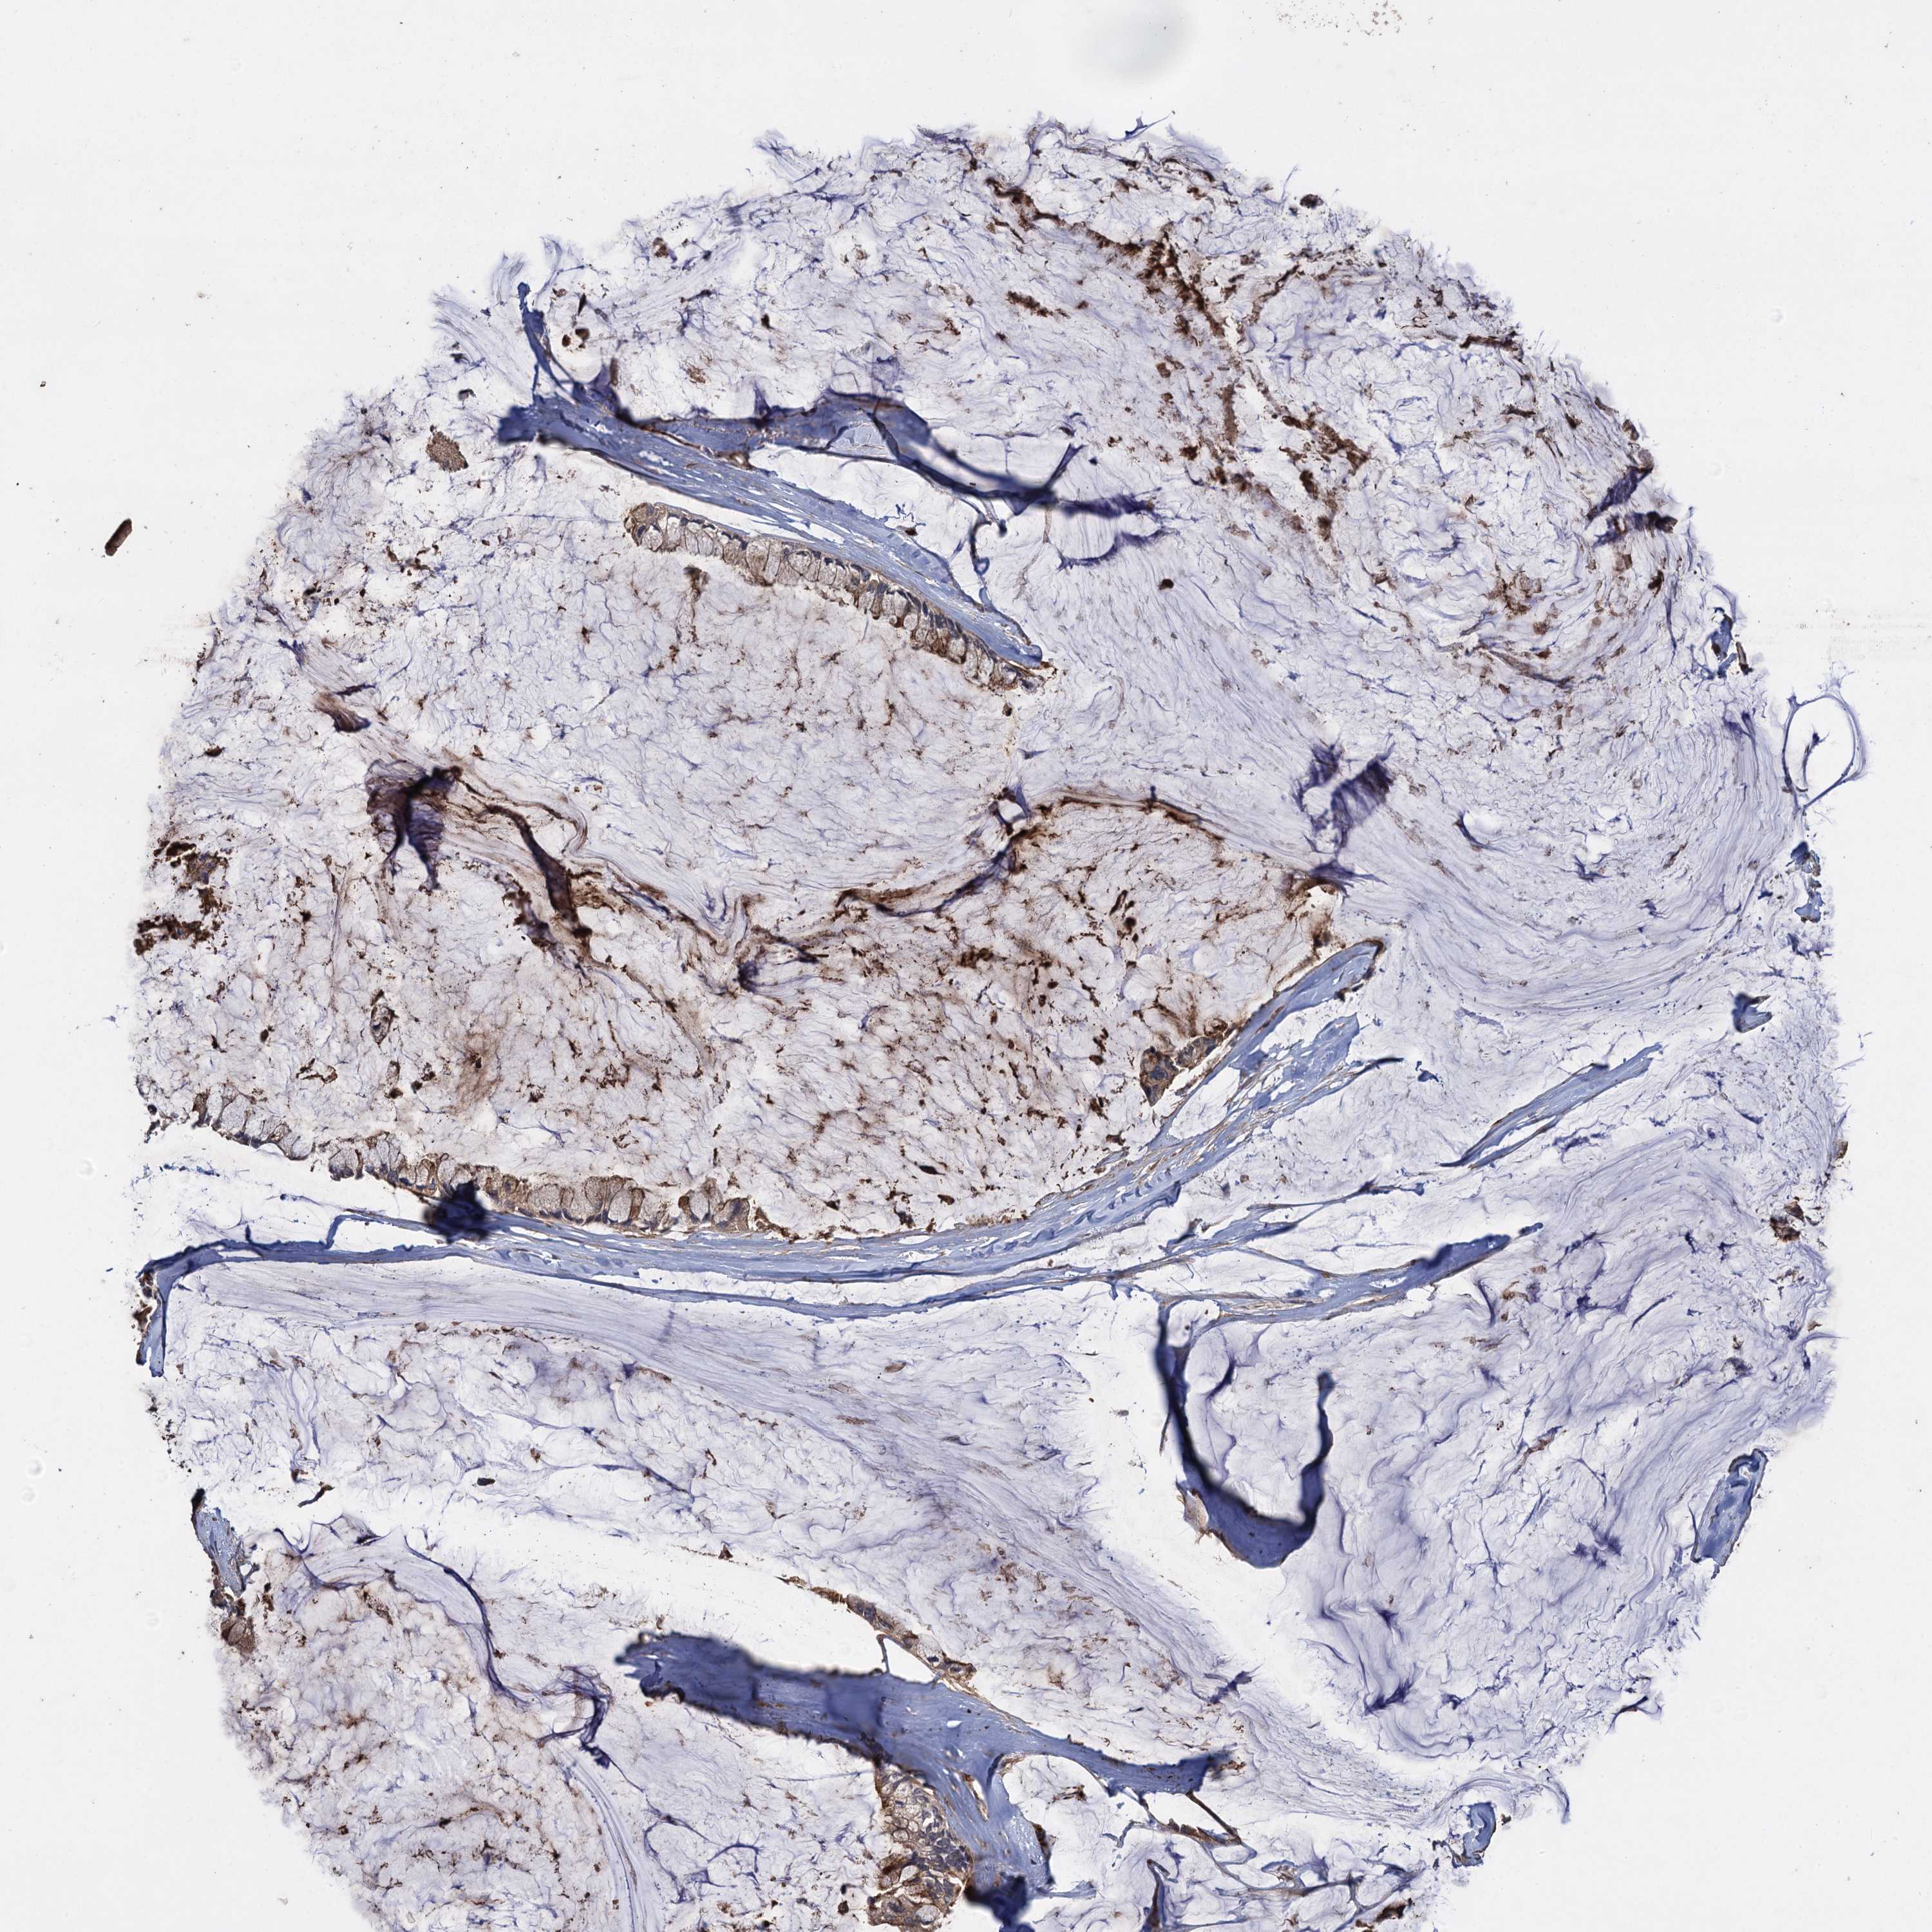

OVARIAN CANCER - Protein expressioni

A mouse-over function shows sample information and annotation data. Click on an image to view it in a full screen mode. Samples can be filtered based on level of antibody staining by selecting one or several of the following categories: high, medium, low and not detected. The assay and annotation is described here.

Note that samples used for immunohistochemistry by the Human Protein Atlas do not correspond to samples in the TCGA dataset.

Antibody stainingi

Antibody staining in the annotated cell types in the current human tissue is reported as not detected, low, medium, or high, based on conventional immunohistochemistry profiling in selected tissues. This score is based on the combination of the staining intensity and fraction of stained cells.

Each image is clickable and will lead to virtual microscopy that enables deeper exploration of all samples and also displays staining intensity scores, fraction scores and subcellular localization as well as patient and tissue information for each sample.

Antibody HPA041174

Antibody HPA041390

Cystadenocarcinoma, serous, NOS

Carcinoma, endometroid

Cystadenocarcinoma, mucinous, NOS

Carcinoma, NOS